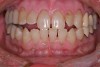

Figure 12  Case three retracted view. Note the rotation of the canine and lingual inclination of the premolars. Posterior disclusion in a lateral movement is not possible.

Figure 12

Patients often become concerned about the long-term viably of their teeth due to failing restorations. This patient was unhappy with the esthetics of her smile due to failing restorations and color. Unfortunately the patient’s anterior guidance was less than ideal due to her current tooth position. The axial inclination of her premolars was biased to the lingual. This tipping of the buccal cusps meant that in an excursive movement, the posterior teeth could not disclude. In addition, the canine teeth were rotated, leaving a deficit of needed contour (Figure 12).

The patient’s 10 anterior teeth all had failing restorations and decay discovered during clinical and radiologic examination. During a diagnostic work-up, it was determined that minor contour changes in the final restorations would allow proper canine guidance and idealized lingual anatomy. A wax-up was created to determine ideal incisal positions (Figure 13), which were then transferred to the mouth in provisionals (Fill-in, Kerr) (Figure 14 through Figure 16). The small contour changes in the restorations allowed proper anterior guidance to be established.